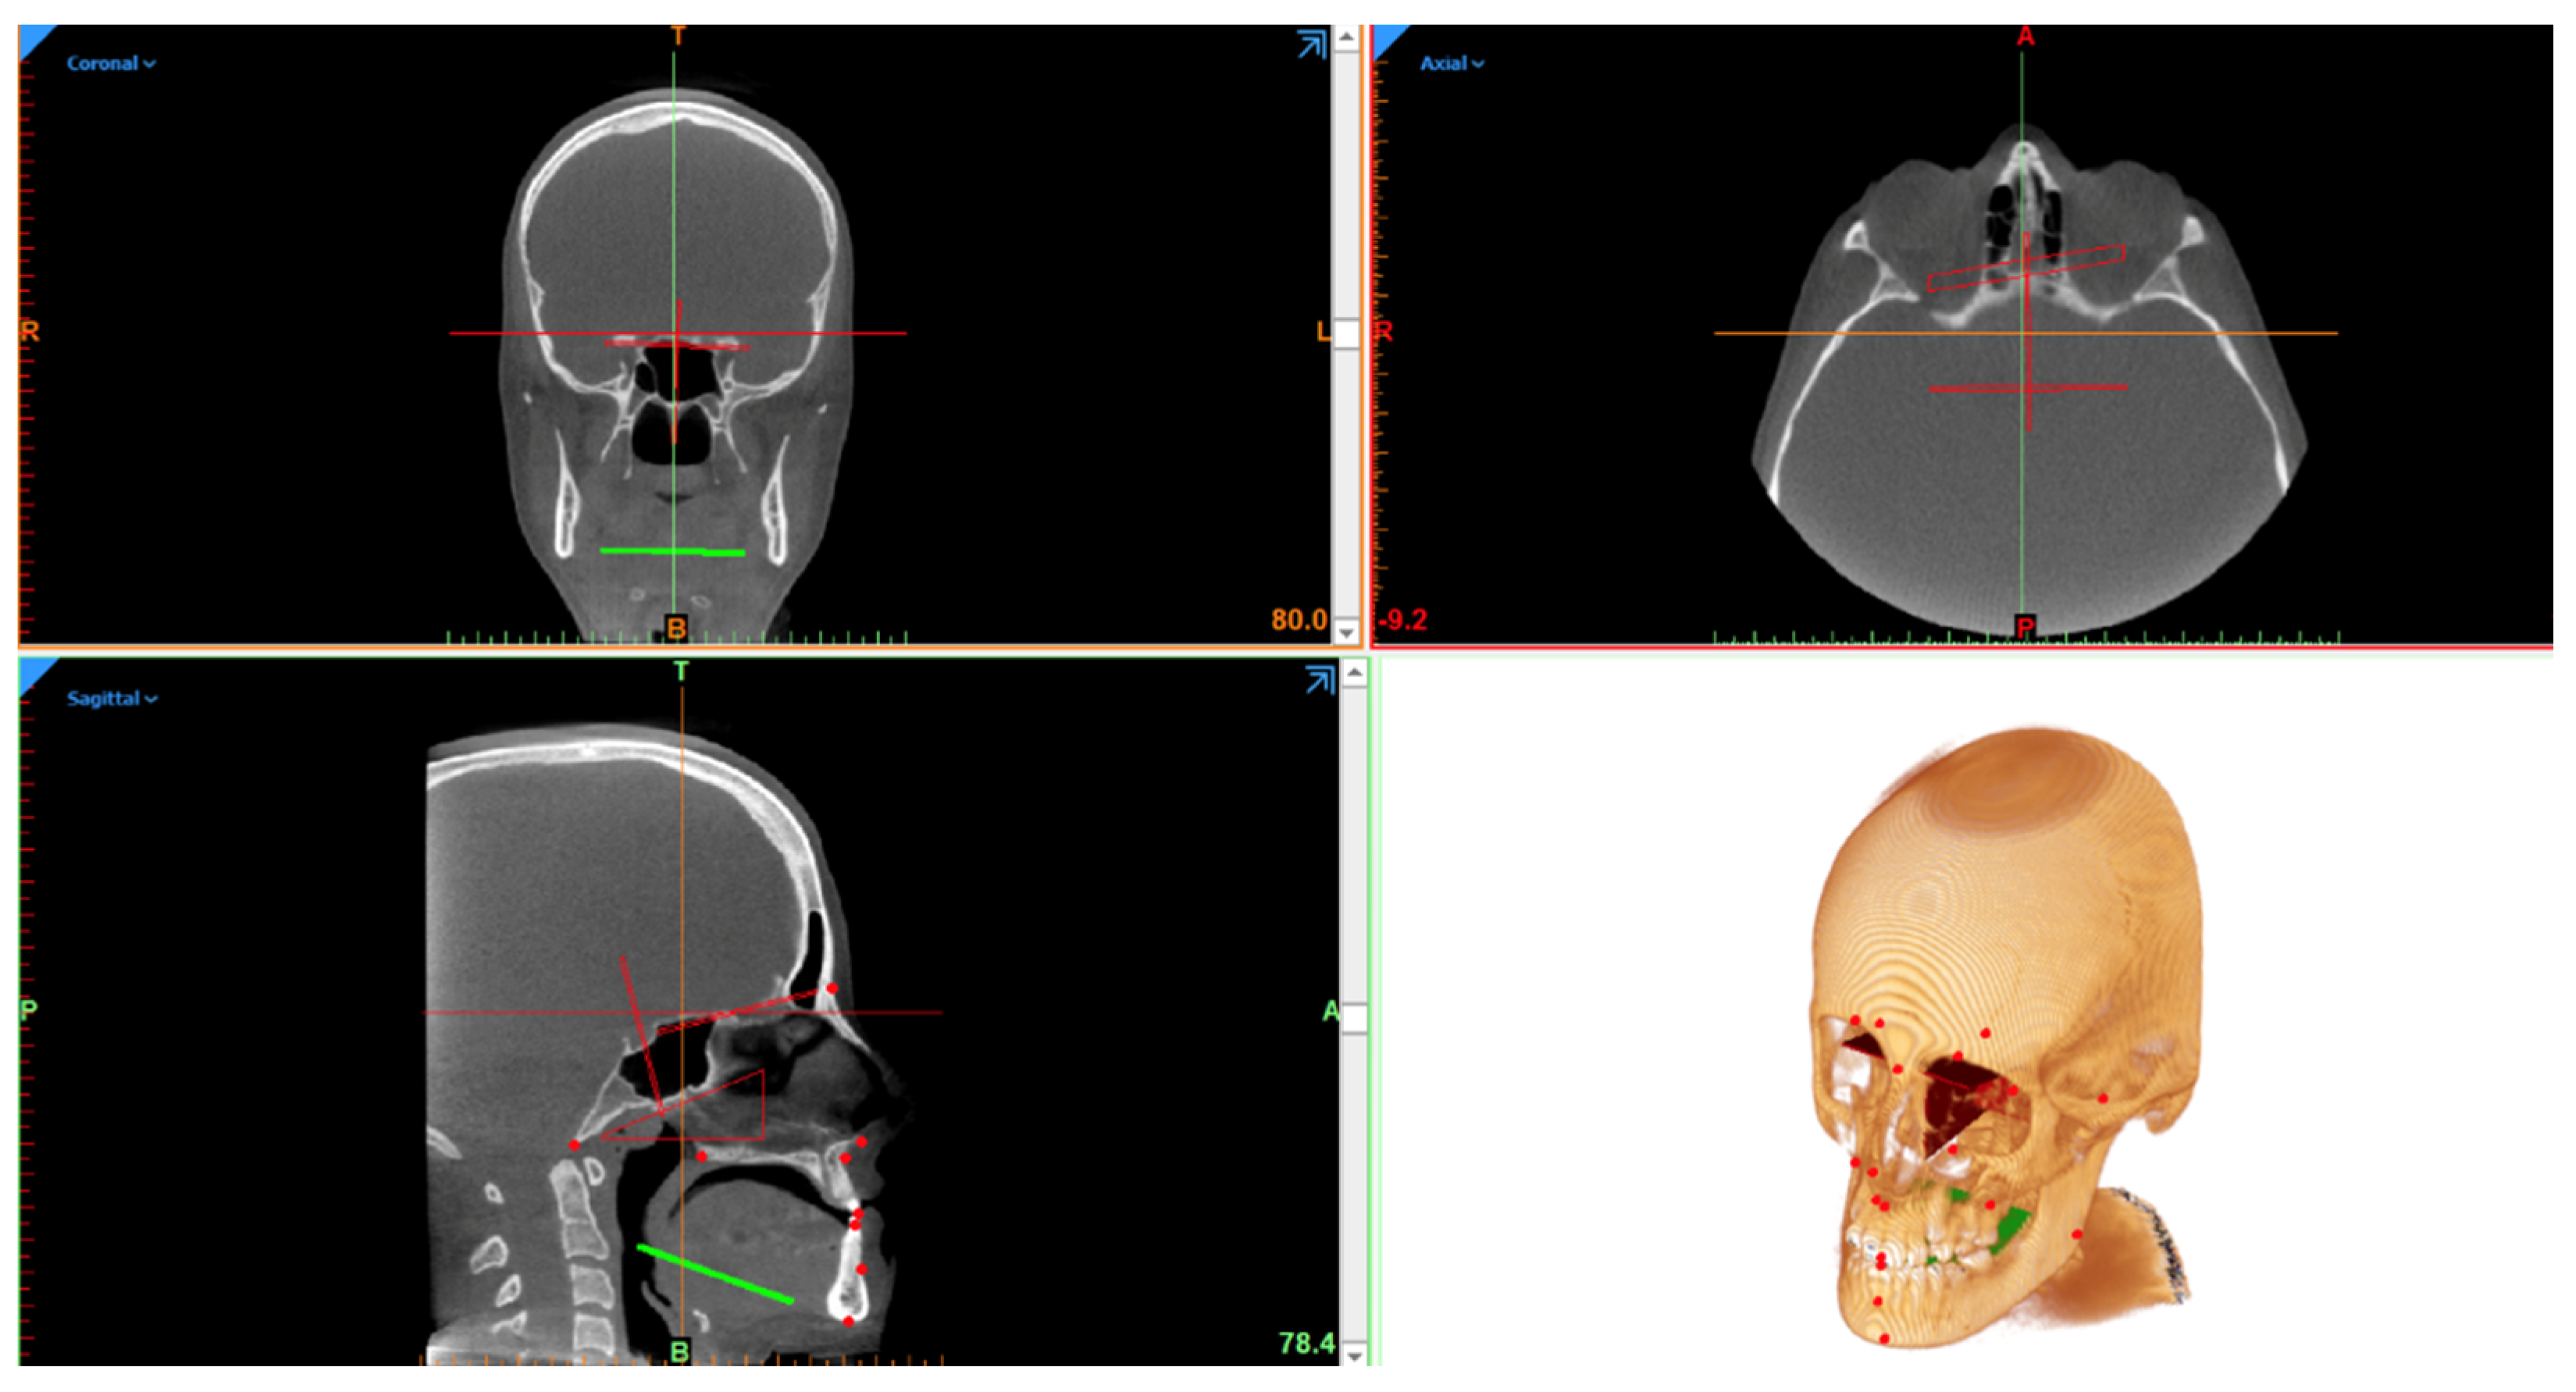

Eighteen cephalometric landmarks were defined using Mimics 22.0 (Materialise, Leuven, Belgium), according to the classical Steiner methods [15] (Figure 1).

Figure 1.

Figure representing the full 3D cephalometry multi-planar vision and three-dimensional reconstruction.